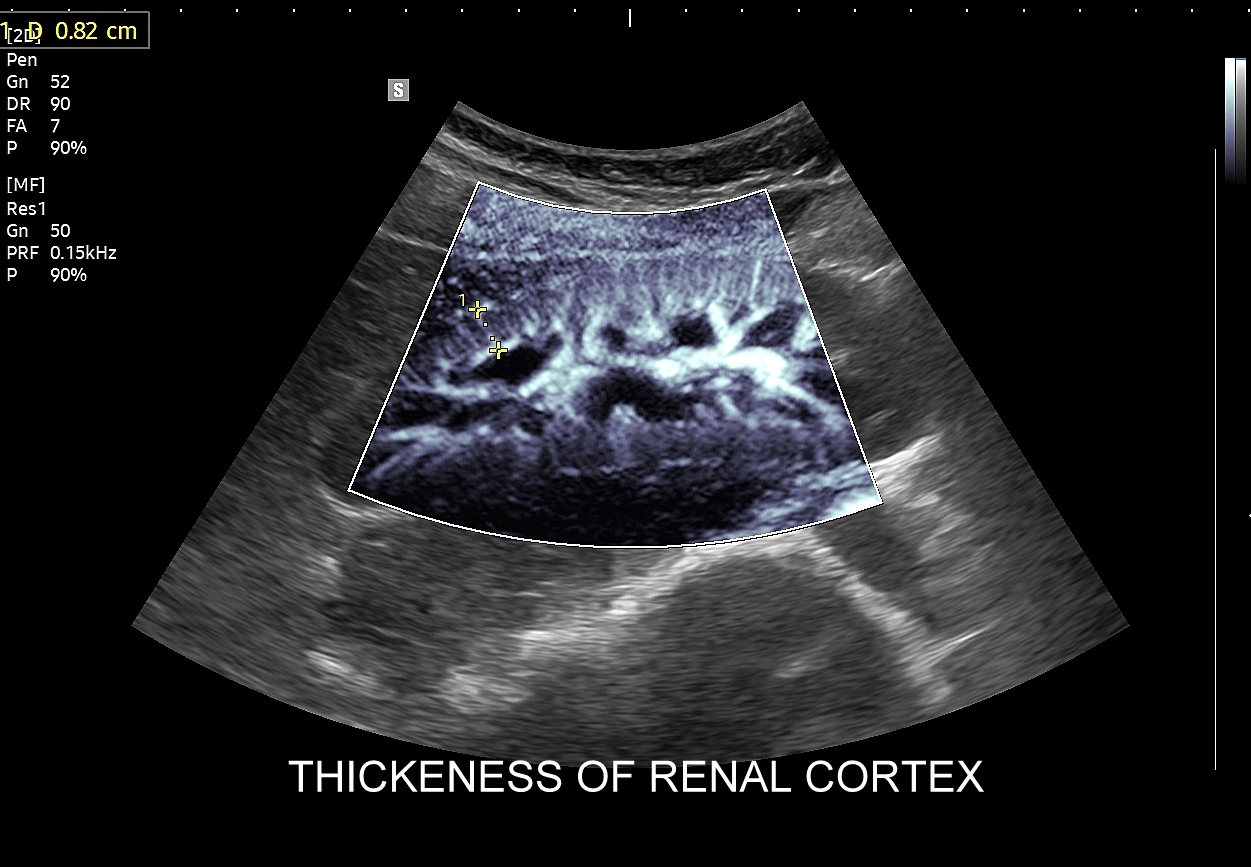

34. Niewydolność nerek w obrazowaniu USG. Funkcjonalna ocena funkcji nerek z zastosowaniem mikroflow i Doppler.

- Badanie USG przepływów nerkowych.